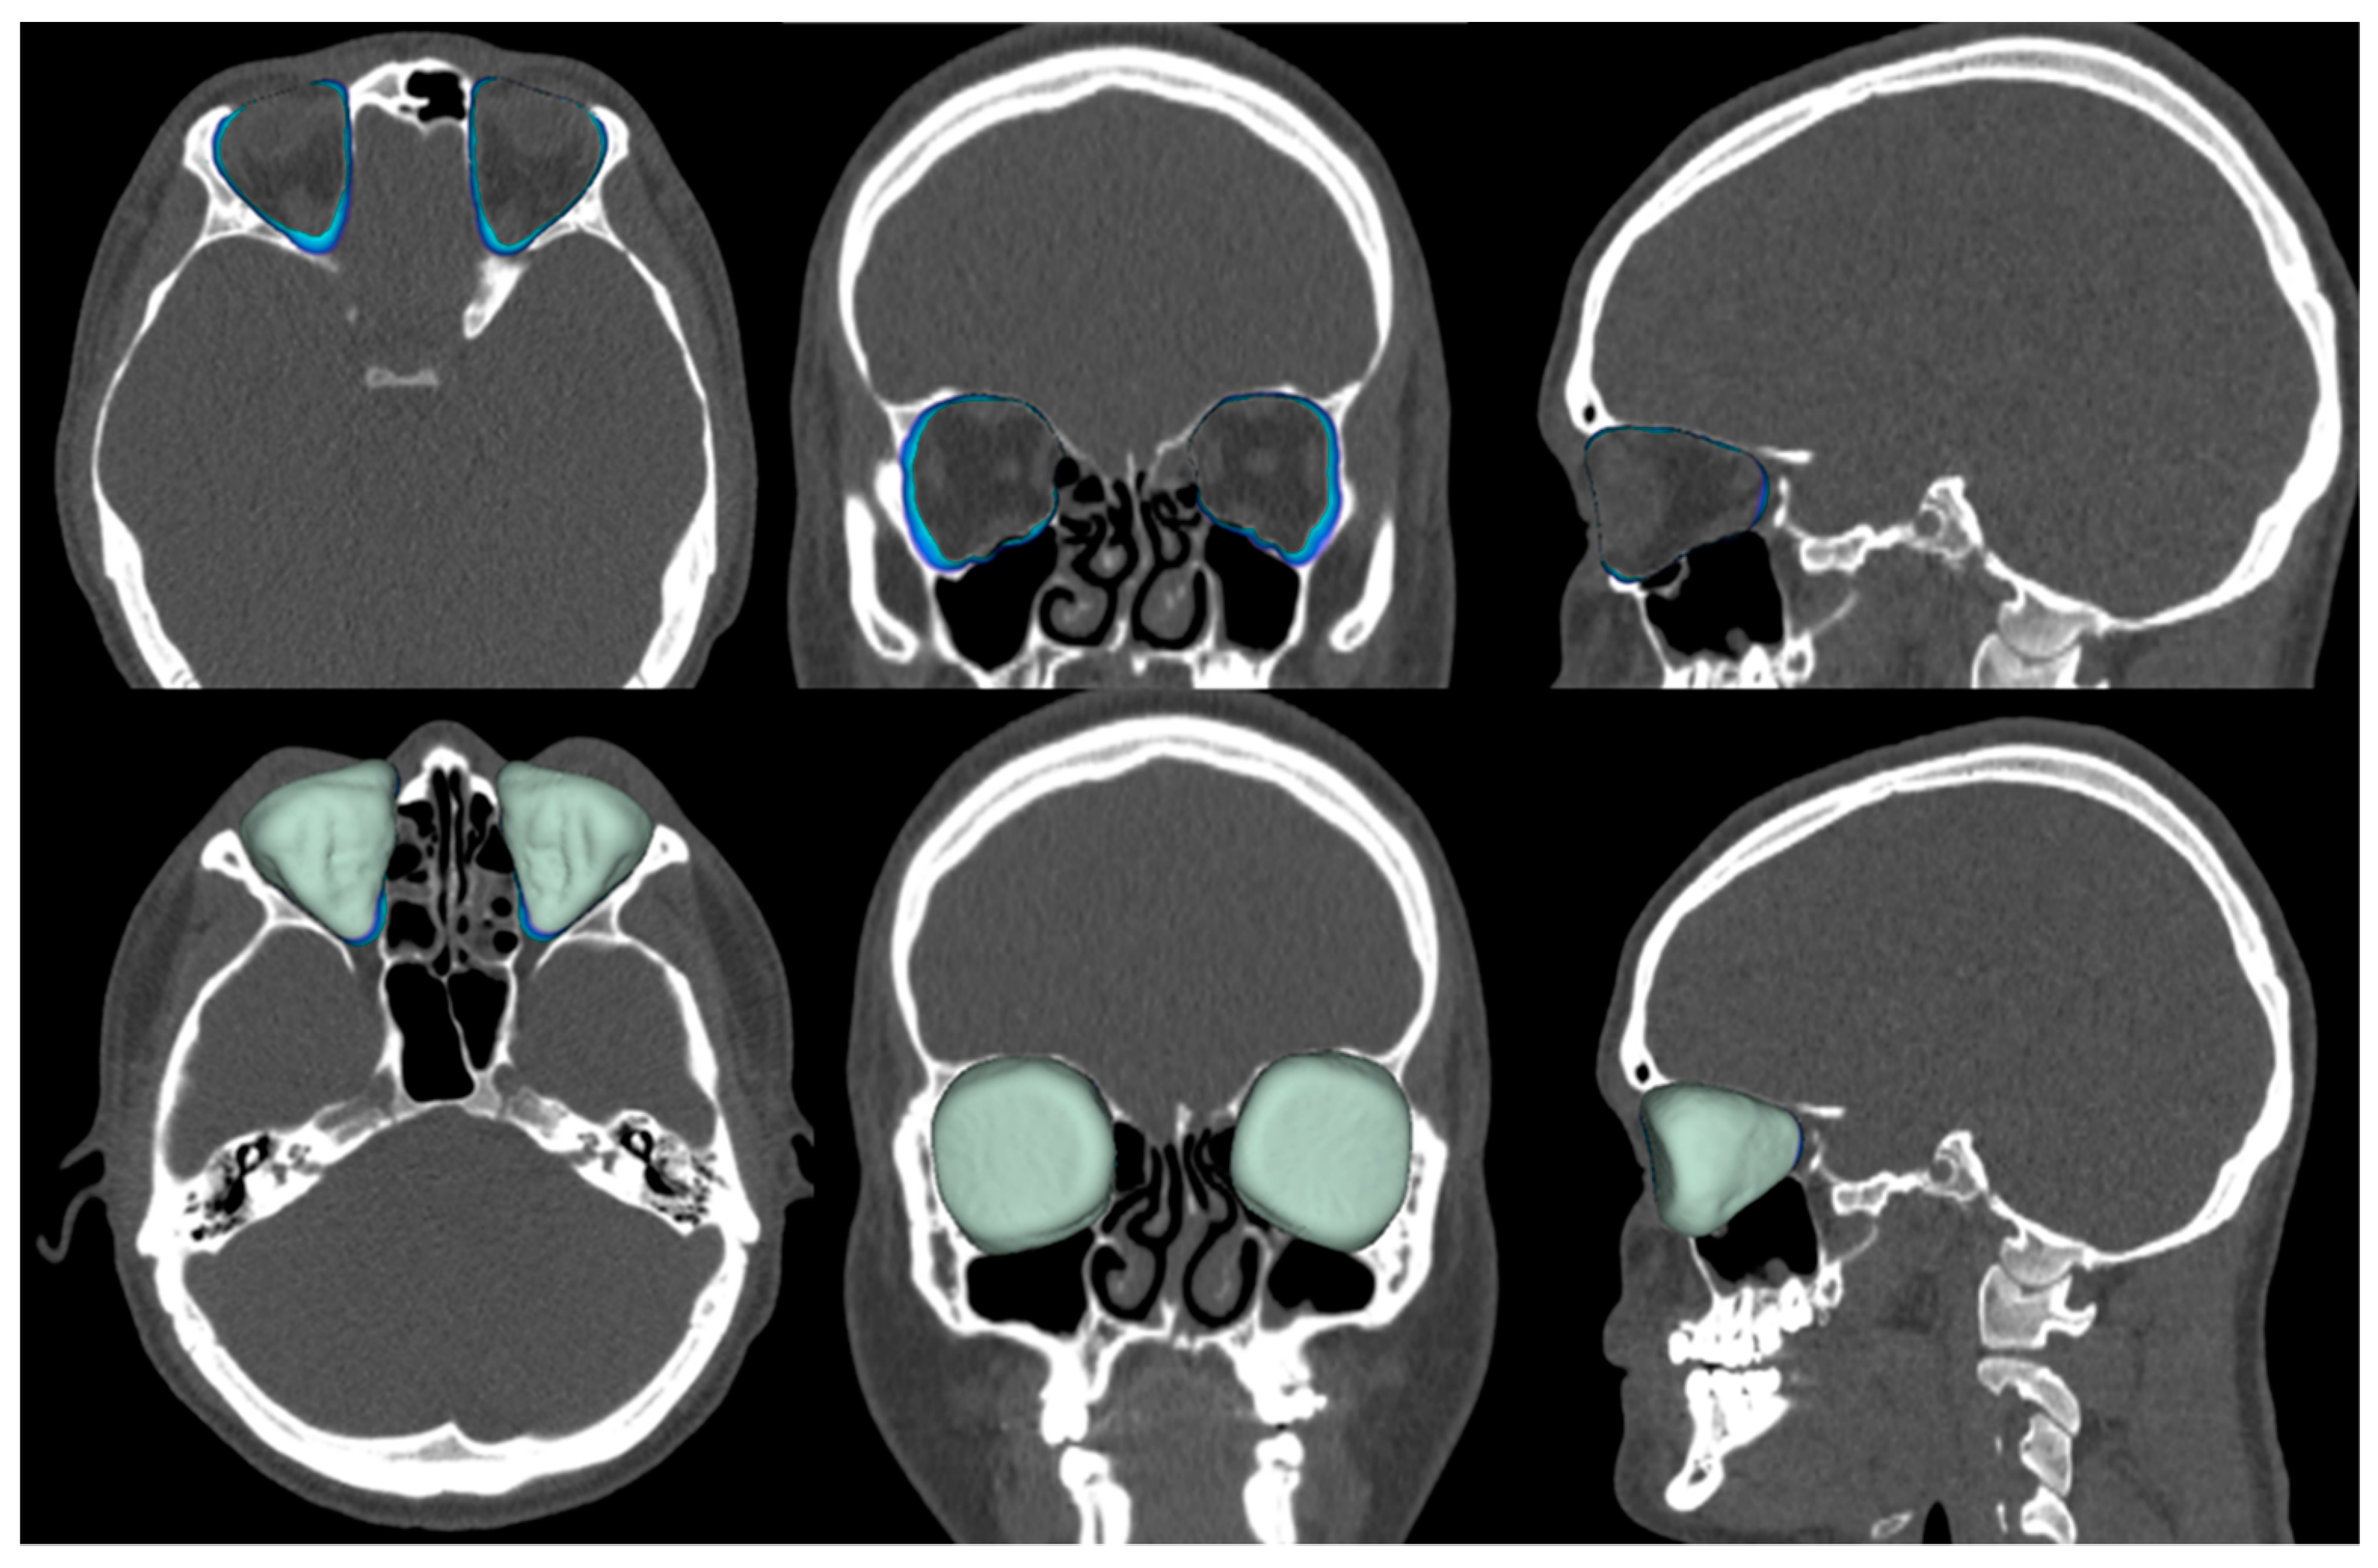

Figure 3.

Assessment of the volume of the bony orbit in the cleft group. Top row contours, and bottom row colors.

To assess non-cleft group asymmetry, the same linear measurements for the cleft group were made by the radiologist (N.L.). Volume was measured as described earlier [26]. Briefly, measurements were made with manual segmentation by defining the contours of the orbit and using 3D segmentation and volume measurement tools. Päijät-Häme Central Hospital radiologist workstations and GE HealthCare AW Server software were used for the analysis according to the manufacturers’ instructions for quantitative analysis.